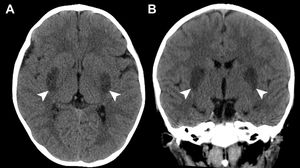

Niño de dos años y un mes acudió con varios días de fiebre, vómitos, irritabilidad y debilidad progresiva en las extremidades. A su llegada se encontraba somnoliento (escala de coma de Glasgow [GCS] E3 V3 M5) y hemodinámicamente estable. La analítica fue anodina, mientras que la prueba de antígenos respiratorios fue positiva para adenovirus. La tomografía computarizada (TC) cerebral sin contraste mostró hipodensidades simétricas bilaterales en los ganglios basales (fig. 1). El paciente fue ingresado en la unidad de cuidados intensivos por deterioro progresivo del nivel de conciencia. Los resultados del análisis del líquido cefalorraquídeo fueron anodinos, y los cultivos bacterianos y virales, negativos. Se administraron inmunoglobulina intravenosa, bolos de corticoides, manitol y cuidados de soporte. Posteriormente, en la resonancia magnética (RM) se observó restricción simétrica de la difusión en los ganglios basales (fig. 2), compatible con encefalopatía necrosante aguda de la infancia. El estudio metabólico descartó errores innatos del metabolismo. El paciente recibió el alta clínicamente estable, con alteración del lenguaje y labilidad emocional residuales.

La encefalopatía necrosante aguda de la infancia es una encefalopatía fulminante asociada a infecciones, que presenta una mortalidad alta y secuelas importantes a largo plazo entre los supervivientes1. Las lesiones simétricas de los ganglios basales y el tálamo son signos radiológicos característicos y se aprecian mejor en la TC y la RM ponderada en difusión (DWI)2. Debido al mal pronóstico de esta enfermedad, aun con tratamiento, resulta esencial reconocer rápidamente estos hallazgos característicos en el ámbito de urgencias para poder intervenir a tiempo y maximizar la probabilidad de una evolución favorable3.